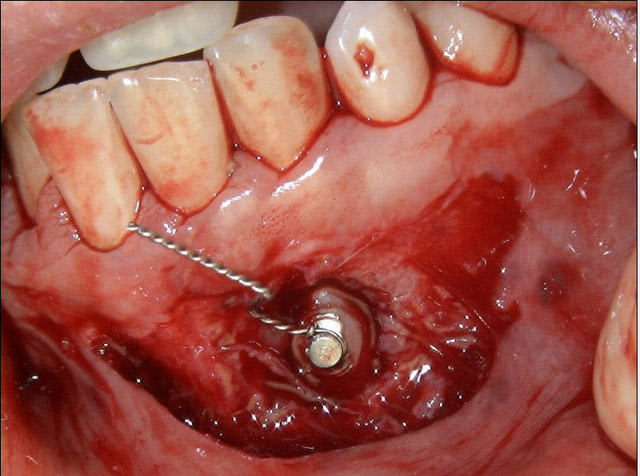

J’avais comme toi un doute avant d’aller la chercher et je me demandais si je n’allais pas avoir quelques difficultés à cause des incisives. En fait, j'ai dégagé relativement facilement sa couronne devant la 32. Elle est donc bien vestibulaire sans contestation possible.

Voici une photo per-op où on voit parfaitement sa situation. C’est la première photo faite, j’avais d’abord fixé une ligature, puis l’ai remplacée par un TMA pour pouvoir exercer un bras de levier vestibulaire.

Le téléprofil ici est trompeur, car on n’individualise pas bien les incisives.